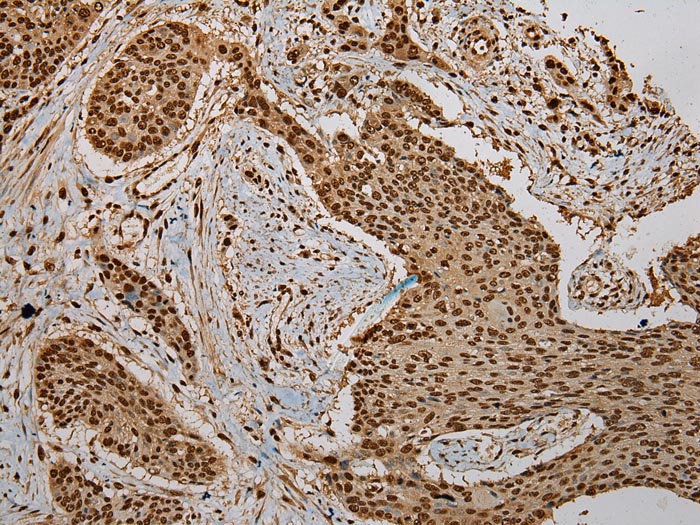

Immunohistochemical analysis of paraffin-embedded Human Breast cancer tissue using #43085 at dilution 1/200.

Immunohistochemical analysis of paraffin-embedded Human Esophagus cancer tissue using #43085 at dilution 1/200.